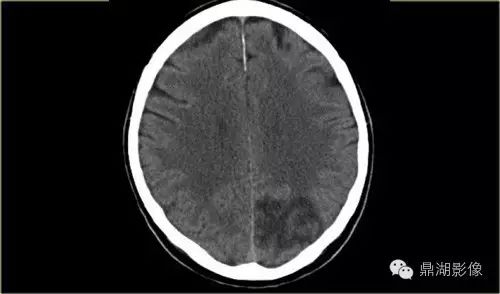

大脑前动脉梗塞

A1:起始部—前交通动脉,发出内侧豆纹动脉,供应尾状核头部和内囊前肢

A2:前交通动脉——胼周动脉——胼缘动脉

A3:皮层支

8be3878cf56b252dfbde23d2cdff9e4f.jpg